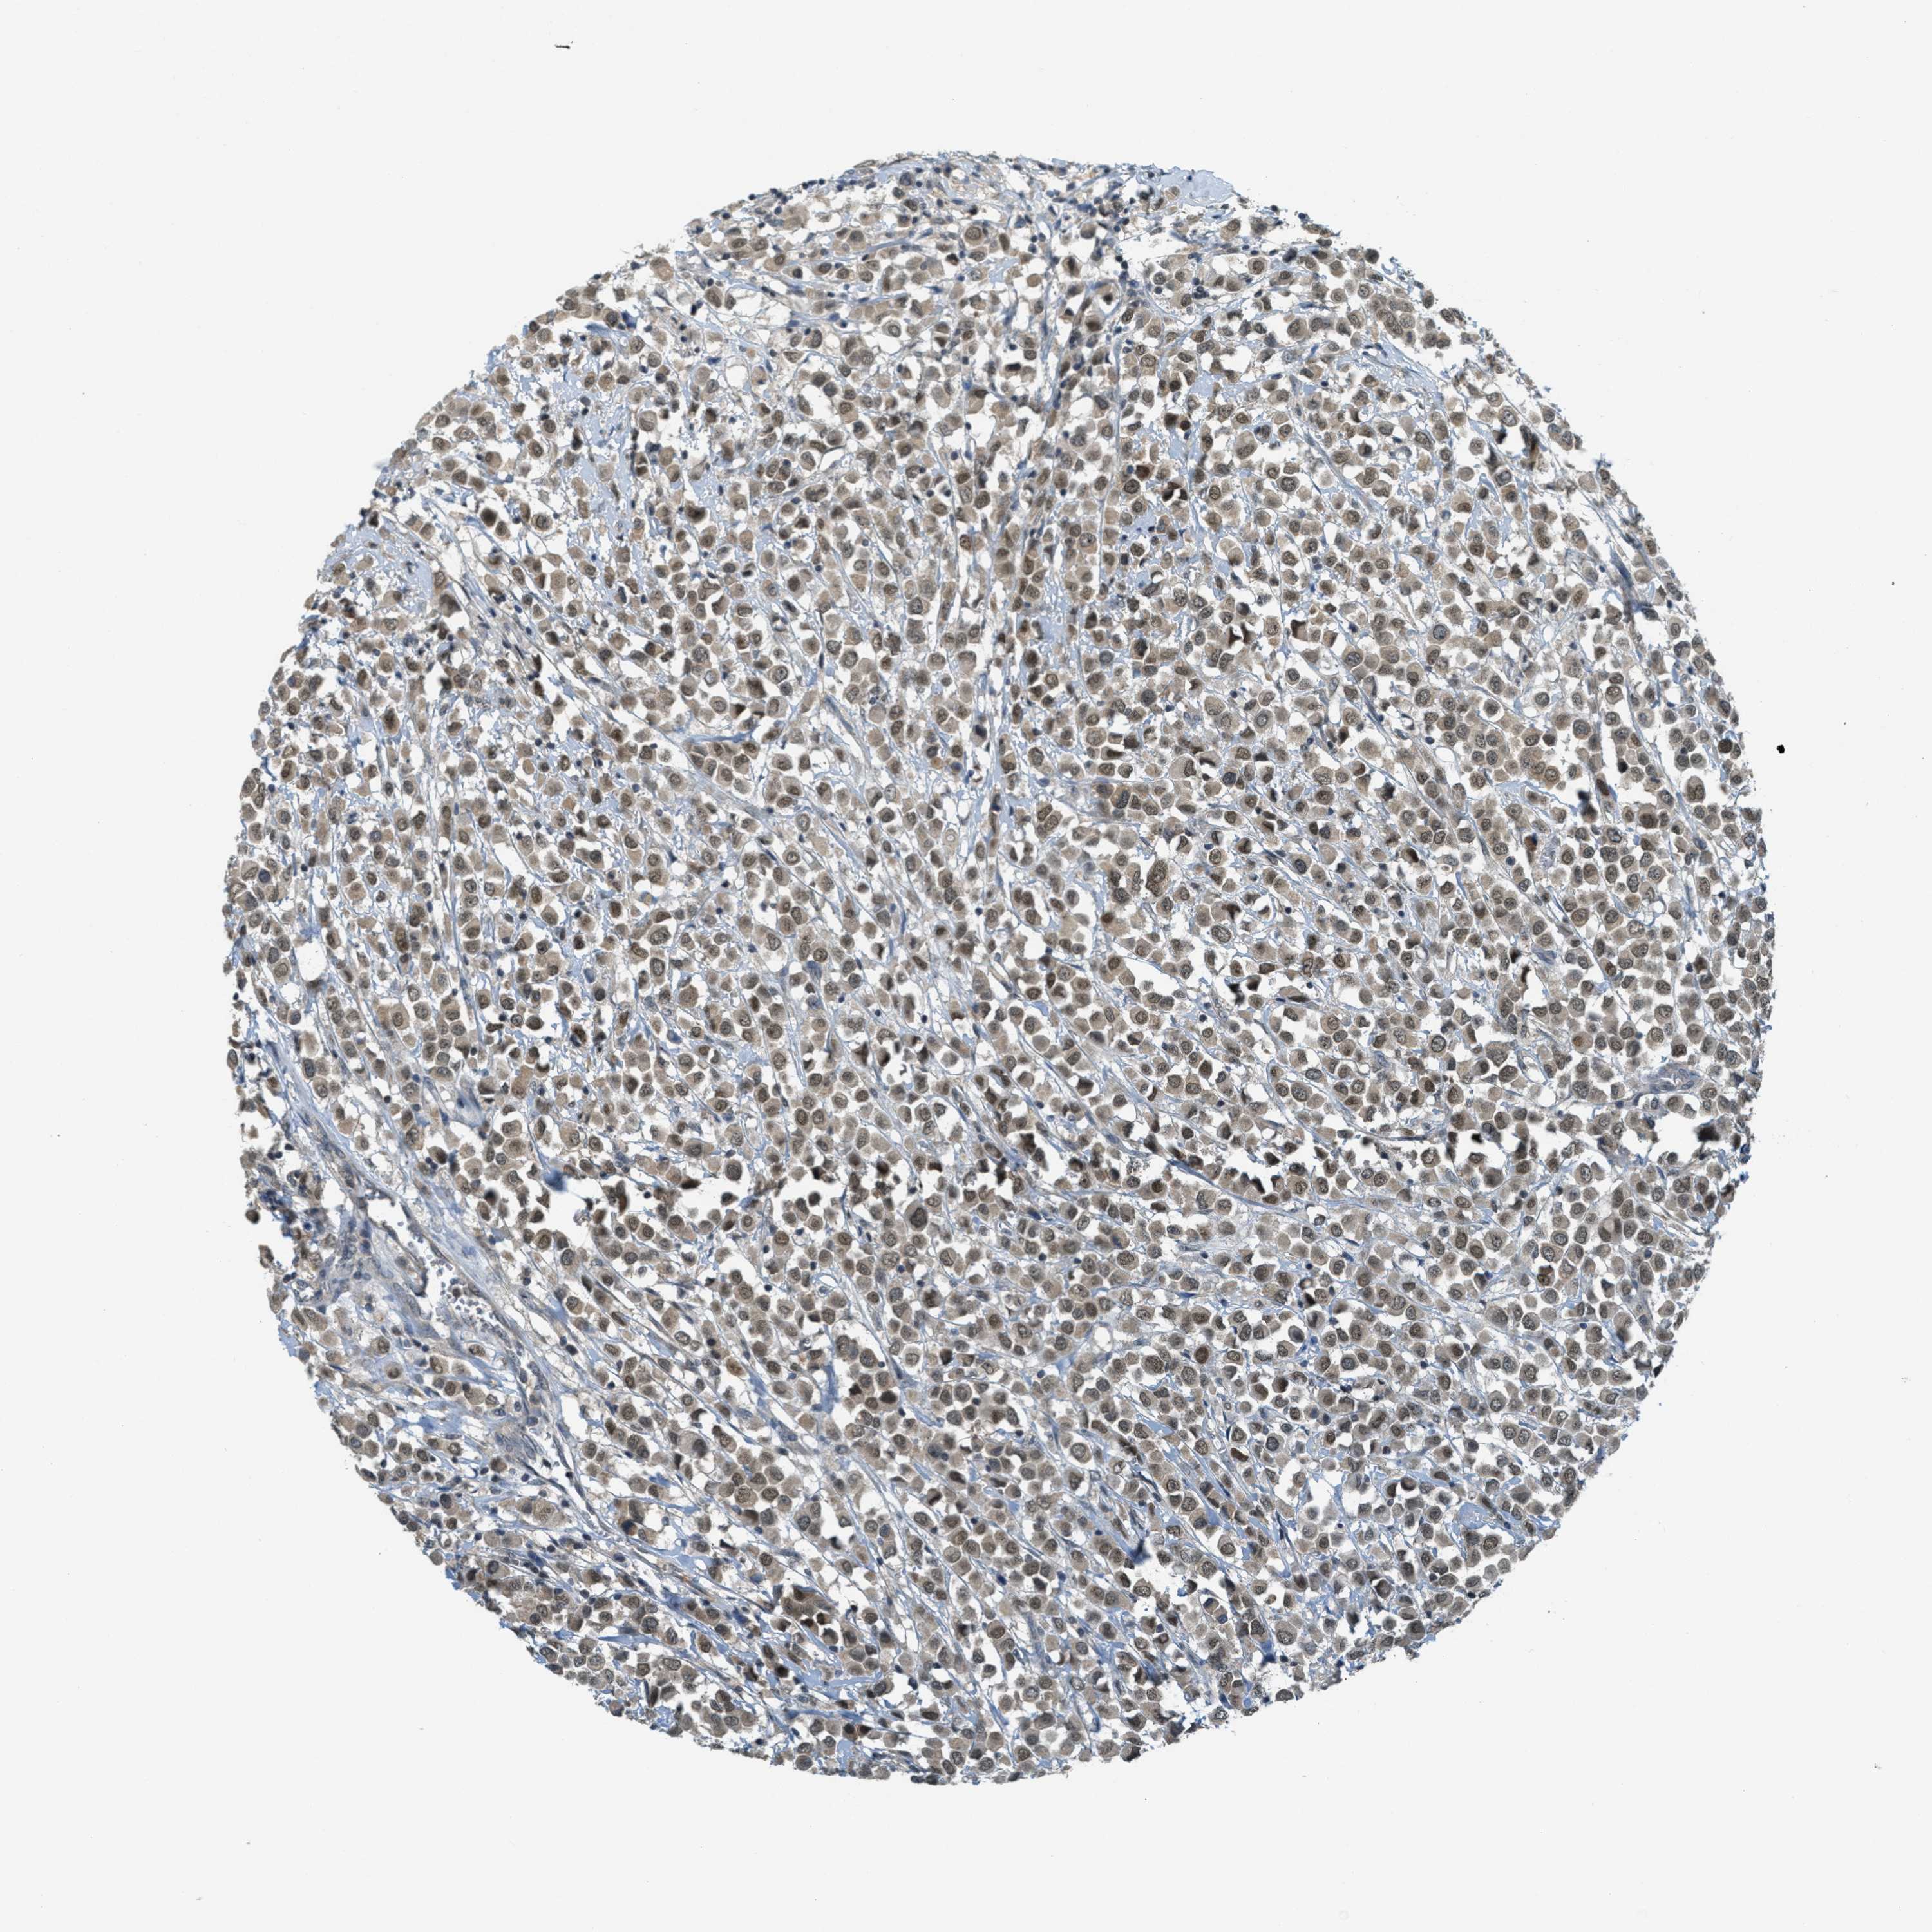

CANCER BREAST CANCER Show tissue menu

BRCA TCGA BRCA VALIDATION PROTEIN EXPRESSION